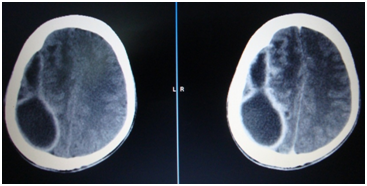

In the presence of clinical mastoiditis, a CT scan should be performed to evaluate for an unappreciated subperiosteal abscess or coalescent mastoiditis (Figure 1 & Figure 2). MRI is also useful in mastoiditis cases (Figure-3), but it is not done routinely. CT scan can demonstrate subperiosteal abscess and possibly the cortical defect in the mastoid.

Figure 1 CT scan picture showing mastoiditis changes on the left side.

Figure 2 CT scan picture of the temporal bone showing soft tissue mass in the mastoid cavity.